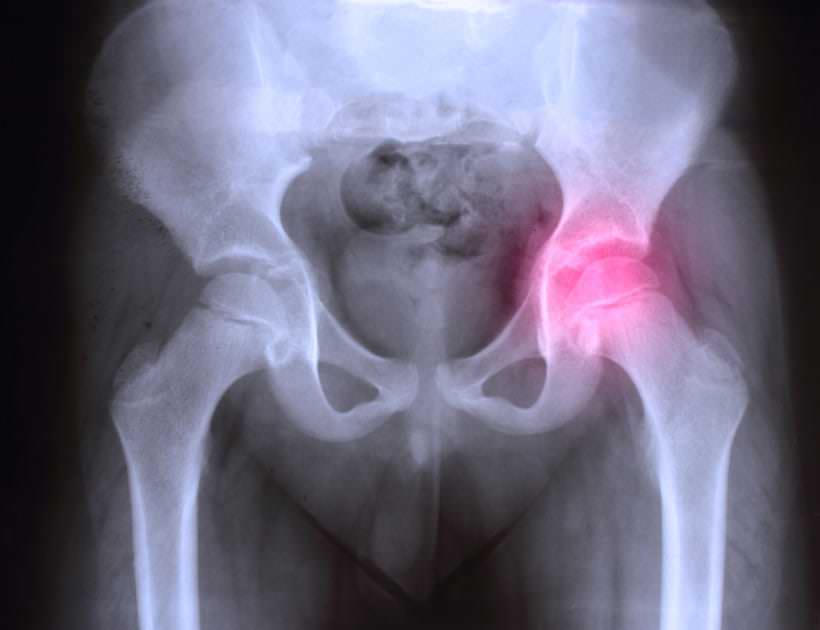

La fracture du col du fémur, aussi appelée « fracture de la hanche », est une fissure qui intervient près de l’articulation de la hanche après un choc. Les fractures du col du fémur sont très fréquentes chez les personnes âgées dont les articulations et plus particulièrement le bassin sont fragilisées avec le temps.

Elles surviennent souvent après l’âge de quatre-vingts ans à l’occasion d’un traumatisme minime, telle une simple chute. Elles entraînent alors des douleurs importantes et la personne ne peut plus bouger la jambe, ni marcher. Cependant, il arrive que la fracture du col du fémur survienne spontanément et c’est alors elle qui provoque la chute. Dans ce cas, les symptômes sont plus difficiles à identifier. Une radiographie sera nécessaire pour confirmer le diagnostic.

- la fracture cervicale, celle qu’on appelle la fracture du col du fémur. Si les fragments du col du fémur cassé ne sont pas l’un en face de l’autre, on parle de fracture déplacée. Ce déplacement peut entraîner une nécrose de la tête fémorale (partie en vert sur la photo ci-dessous). En résultent des douleurs au niveau de la hanche et des problèmes d’articulation. ;

- la fracture trochantérienne, située sur le massif trochantérien (c’est-à-dire plus bas sur l’os fémoral du membre inférieur, aussi appelé trochanter).